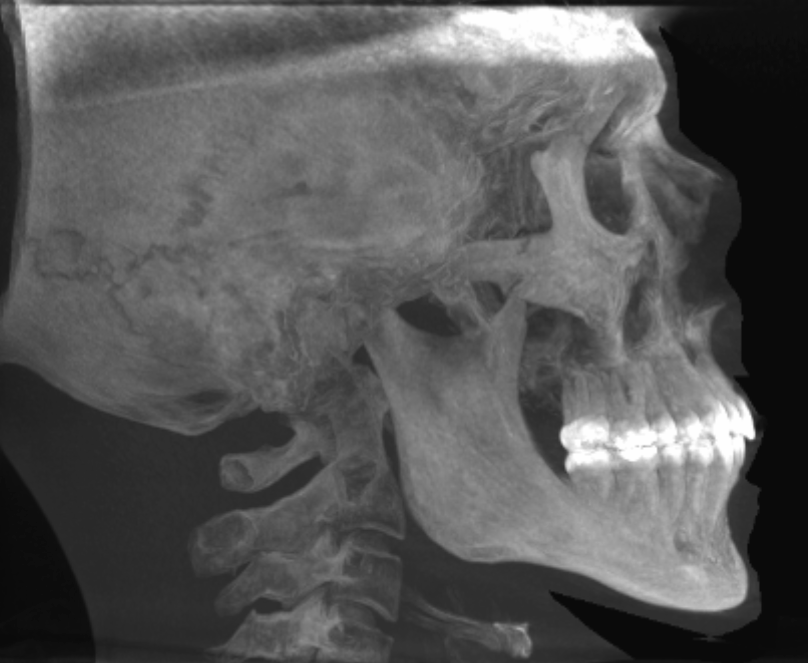

Rate this CT scan (profile, forward, 45deg)

soft tissue removed. tell me how my bones look.

narrow jaw, and kinda short chin.

you're not recessed, frankfurt plane is okay. gonions are a little bit high but not a big problem.

gonions are outward, that is really important.

is it my impression or do you got downward growth?

>is it my impression or do you got downward growth?

maybe. i have gummy smile. jaw surgeon said it seemed mostly due to soft tissue, but offered le fort 1 anyway to keep my options option. i'm tryna to decide best option and see if jaw surgery is needed for other reasons too... two birds, one stone etc